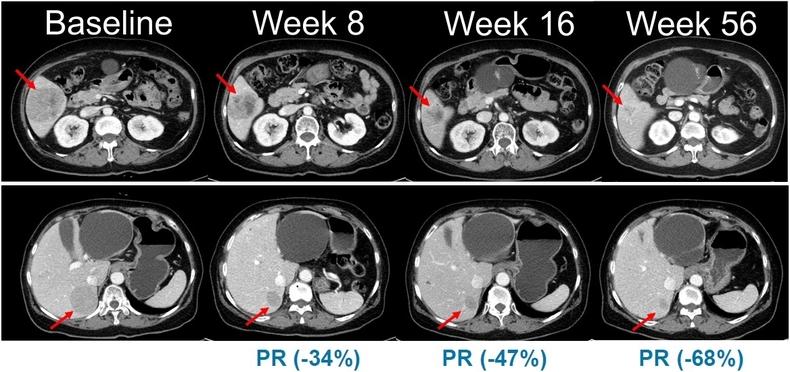

국내외 치료제 없는 NRAS 돌연변이 흑색종 환자서 유의미한 항종양 효능

이번 임상 2상은 총 45명의 환자를 대상으로 표적 항암신약 벨바라페닙과 MEK 억제제인 코비메티닙(Cobimetinib) 병용요법의 유효성과 안전성을 평가하기 위한 다기관, 단일군 시험으로 진행된다.

특히 NRAS 돌연변이 흑색종은 예후가 불량하고 국내외 허가된 표준 치료제가 없는 의료적 미충족 수요가 높은 영역으로, 현재 의료 현장에서는 벨바라페닙이 치료목적사용 승인을 통해 일부 환자에게 제한적으로 투약되고 있다.

한미약품이 최초로 개발한 벨바라페닙은 종양 세포의 성장과 증식에 관여하는 미토겐 활성화 단백질 키나아제(mitogen-activated protein kinases, MAPK) 경로 중 RAF 및 RAS 유전자 돌연변이를 타깃해 억제하는 경구용 표적 항암제다.

벨바라페닙은 RAF 이합체(dimer)를 선택적으로 저해하는 차별화된 기전을 토대로 BRAF ClassⅡ/Ⅲ 변이와 RAS 변이를 보유한 종양을 표적한다. 기존 BRAF 저해제가 주로 단일체(monomer)만을 억제하는 것과 달리, 벨바라페닙은 BRAF 및 CRAF 이합체까지 함께 억제하도록 설계돼 RAF 이합체 형성에 따른 내성 문제를 극복할 수 있도록 개발됐다.

이에 따라 벨바라페닙과 코비메티닙의 병용요법은 기존 BRAF 단일체와 MEK 억제제 병용 치료의 기전적 한계를 극복하고, 보다 폭넓은 유전자 변이 환자군에서 임상적 이점을 제공할 수 있는 치료 전략으로 평가된다.